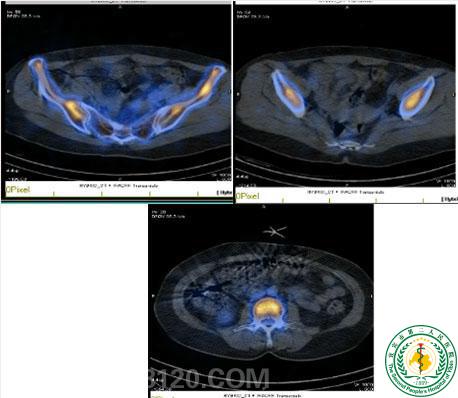

肿瘤中心研究成果在国际权威Top期刊《cancer》上发表并同时配发特约评论文章

肿瘤中心研究成果在国际权威Top期刊《cancer》上发表并同时配发特约评论文章48942